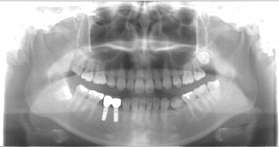

| 院長の母親の症例(10年経過) |

写真の右上の骨がない

写真の右上にモアモアしたところが骨になっているところ |

| 上顎洞挙上した所にインプラント埋入した写真 |